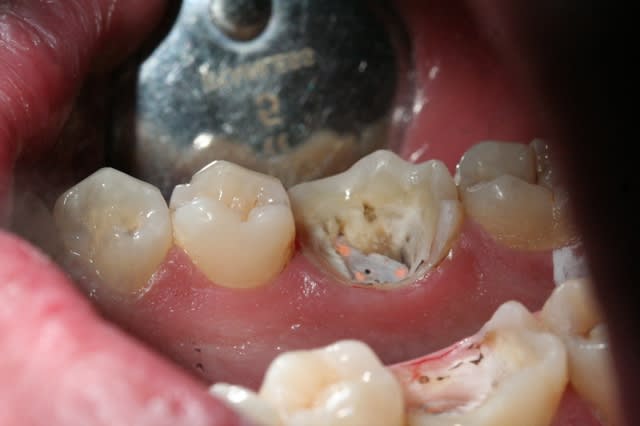

dépose du systemp onlay (trés pratique, se détache bien)

situation clinique

est ce que l'onlay est vraiment une solution sur des dents dévitalisées aussi délabrées que celle ci?

Img 1744 z0evts - Eugenol

je ne suis pas sure non plus que dans ce cas l'indication soit bonne.

Mais non les gars, vous vous trompez!

on le voit peut être mal sur les photos mais il reste encore pas mal de tissu dentaire à conserver avant de se jeter comme un loup sur une brebis pour faire une couronne.

Il faut temporiser, proposer d'autres alternatives aux gens. Ici, ce patient n'avait pas de complémentaire, alors entre une ccm à 500 remboursée 96.75 et un onlay à 300 remboursé 35 environ , le patient a choisit.

En l'occurrence, dent dépulpée/2 parois résiduelles il s'agit d'une indication de coiffe périphérique (couronne) et vu les limites à peine juxta, je dirais même ancrage radiculaire...